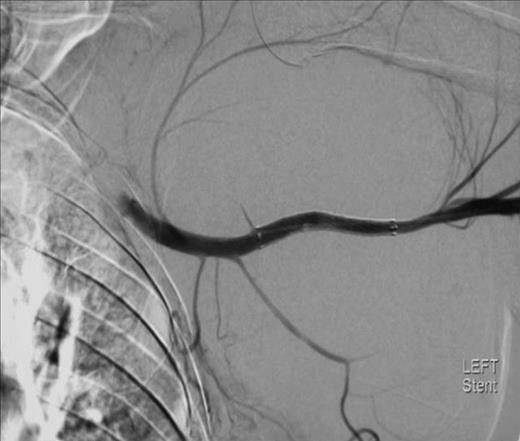

Repeat X-ray of left shoulder demonstrating subluxation of the head of the humerus

To attempt endovascular repair, an operative approach to the brachial artery preceded retrograde insertion of a 6cm long, 8mm thick Fluency nitinol self-expanding PTFE covered stent (Bard). This excluded the lesion successfully (figures 4 and 5). The haematoma was decompressed. Aspirin 75mg and clopidogrel 75mg were initiated for stent protection. The patient suffered a postoperative axillary wound infection which was treated successfully with antibiotics. There had been no recovery of neurological function in the arm. Neurophysiological studies revealed a proximal axonotmesis with a poor prognosis.

The lesion was repaired by an endovascular retrograde approach whereby the neck of the lesion was located just distal to the origin of the subscapular artery and the cavity excluded successfully by the insertion of self-expanding Fluency nitinol PTFE-covered stent (Bard). Such a method was favoured here because the condition of the arm rendered open approaches hazardous. There are several reports of the treatment of such lesions by stent graft, including those of Xenos (10), whilst open repair also offers a simultaneous opportunity to explore for and deal with associated injuries.